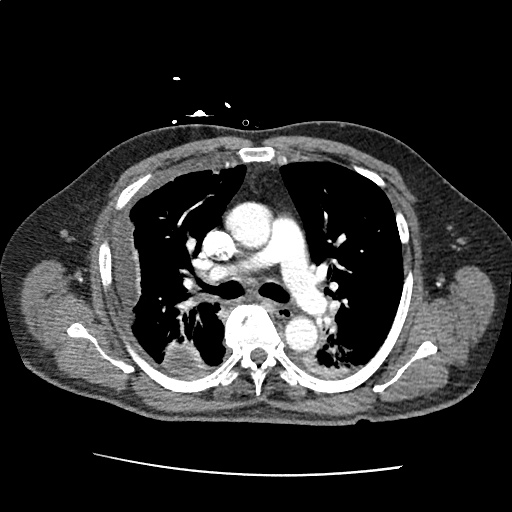

Pleural based mass Radiology Cases Radiology Pleural Tag Chest radiography and us help detect pneumothorax with various signs, and ct can also help assess the causes. Pleural tags were defined as linear strands that extended from the nodule surface to a pleural surface and were classified into three. Juxtapleural lung nodules can be defined by their location within 15 mm of a pleural surface. Radiology Pleural Tag.

Pleural based mass Radiology Cases Radiology Pleural Tag Pleural tags were defined as linear strands that extended from the nodule surface to a pleural surface and were classified into three. Juxtapleural lung nodules can be defined by their location within 15 mm of a pleural surface. Chest radiography and us help detect pneumothorax with various signs, and ct can also help assess the causes. Radiology Pleural Tag.

Pleural based mass Radiology Cases Radiology Pleural Tag Juxtapleural lung nodules can be defined by their location within 15 mm of a pleural surface. Chest radiography and us help detect pneumothorax with various signs, and ct can also help assess the causes. Pleural tags were defined as linear strands that extended from the nodule surface to a pleural surface and were classified into three. Radiology Pleural Tag.